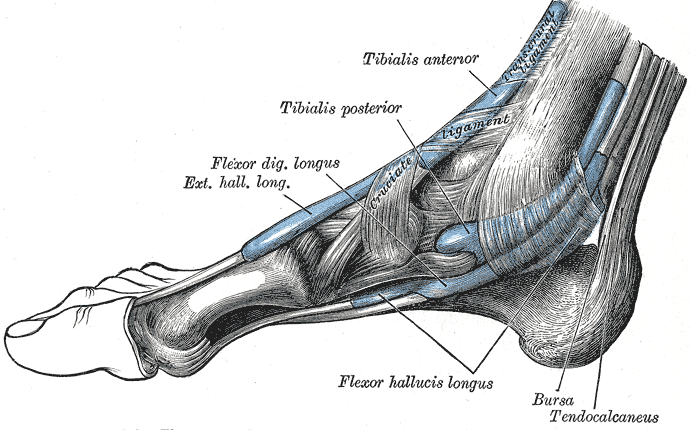

In human anatomy, the fibularis longus (also known as peroneus longus) is a superficial muscle in the lateral compartment of the leg, and acts to evert and plantar flex the ankle. The muscle, the longest and most superficial of the three fibularis muscles, is attached proximally to the head of the fibula and its 'belly' runs down most of this bone. It becomes a tendon that goes posteriorly around the lateral malleolus of the ankle, then continues under the foot to attach to the medial cuneiform and first metatarsal.

It ends in a long tendon, which runs behind the lateral malleolus, in a groove common to it and the tendon of the fibularis brevis; the groove is converted into a canal by the superior fibular retinaculum, and the tendons in it are contained in a common mucous sheath.[2] The tendon then extends obliquely forward across the lateral side of the calcaneus, below the trochlear process, and the tendon of the fibularis brevis, and under cover of theinferior fibular retinaculum.[2] It crosses the lateral side of the cuboid, and then runs on the under surface of that bone in a groove which is converted into a canal by the long plantar ligament; the tendon then crosses the sole of the foot obliquely, and is inserted into the lateral side of the base of the first metatarsal bone and the lateral side of the medial cuneiform.[2] Occasionally it sends a slip to the base of the second metatarsal bone.[2]

The tendon changes its direction at two points: first, behind the lateral malleolus; secondly, on the cuboid bone; in both of these situations the tendon is thickened, and, in the latter, a sesamoid fibrocartilage (sometimes a bone), is usually developed in its substance.[2]

The fibularis longus and brevis muscles plantar-flex the foot, in conjunction with the tibialis posterior, antagonizing the tibialis anterior and fibularis tertius, which are dorsi-flexors of the foot.[2]

The fibularis longus also everts the sole of the foot, and from the oblique direction of the tendon across the sole of the foot is an important agent in the maintenance of the transverse arch.[2]